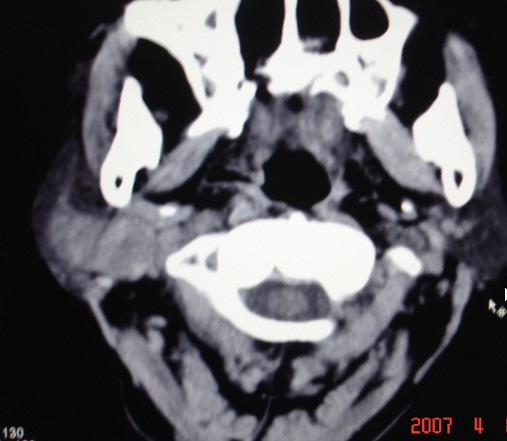

以下是引用zjzjr在2007-4-9 13:27:00的发言:[br]右侧腮腺深浅叶可见一混杂密度区,含有实性及囊性成.考虑右侧腮腺混合瘤,建议ct增强扫描。

以下是引用jiangjing在2007-4-9 15:09:00的发言:[br]考虑右侧腮腺肿瘤[混合瘤可能性大],其他待排[br]建议ct增强扫描。